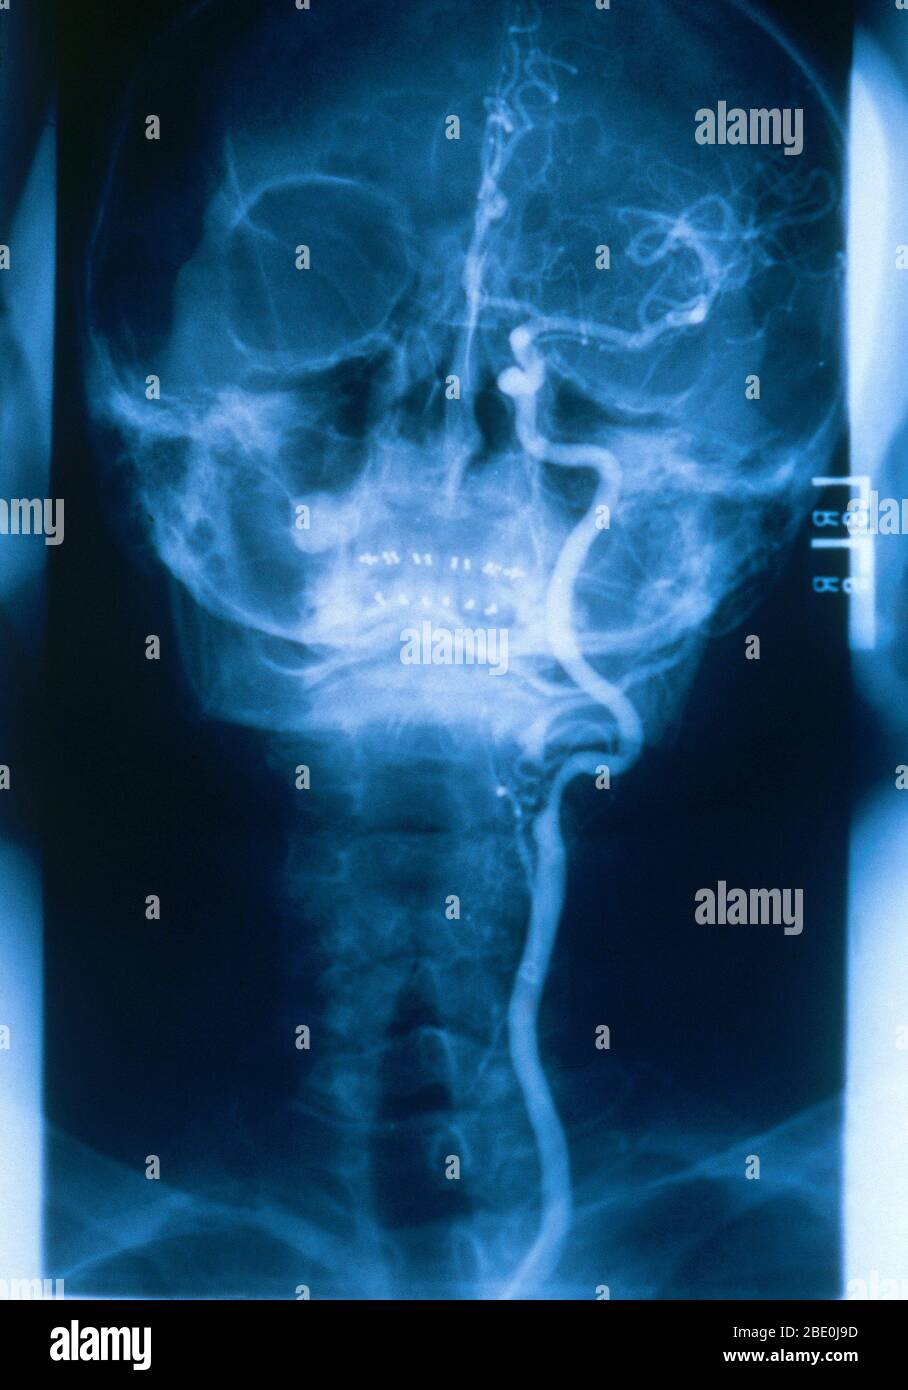

RM2BE1154–Medizinische Radiologie mit einem normalen linken Halsschlagader. Die gemeinsame Halsschlagader versorgt Hals und Kopf mit sauerstoffreichem Blut.

RM2BE0J9D–Medizinische Radiologie mit einem normalen linken Halsschlagader. Die gemeinsame Halsschlagader versorgt Hals und Kopf mit sauerstoffreichem Blut.